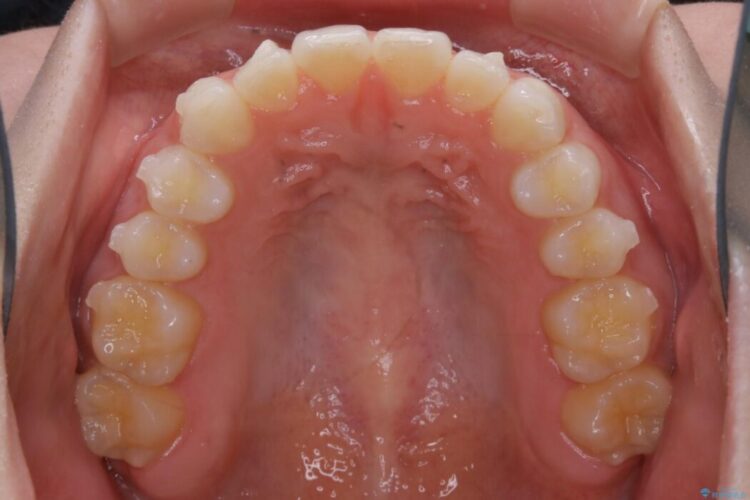

上下前歯のねじれなどで生じている歯列のガタつきをなおしたいとのことで来院されました。

精密検査をしたところ、奥歯に大きな問題がないため移動はほとんど必要がなく、また主訴であるガタつきの改善に必要なスペースも少量であったため、インビザラインのライトパッケージの治療をご提案しました。